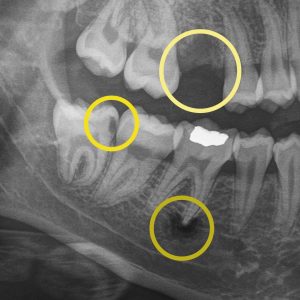

Digital X-rays help your dentist detect concerns early, track changes over time, and personalize your care…